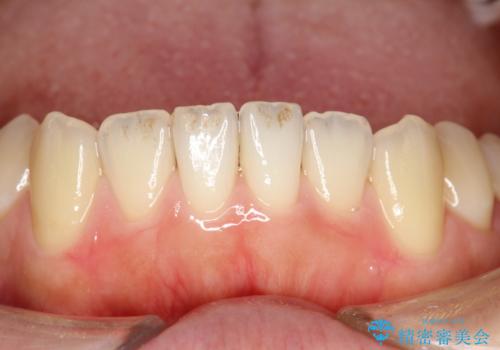

茶渋による汚れをクリーニングできれいに

- 全体の歯にうっすらと茶渋によるステインが見られます。

よく見ると歯自体はあまり黄色くないので、ステインによって歯が黄色く見えてしまっています。

PMTCというクリーニングを行うことでステインは除去できるので、今回はPMTC(エアフロー)の60分コースにて全体のクリーニングを行いました。

エアフローは歯と歯の間や、詰め物との境目などブラシやチップが届かないところまで細かくお掃除が可能になります。

隅々までお掃除することで虫歯や歯周病のリスクを下げる効果があります。